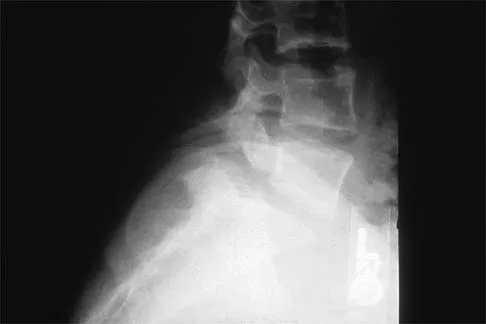

A 19-year-old woman reports lower back pain following a motor vehicle accident. Radiographs obtained immediately after the accident and a bone scan obtained 4 weeks later are shown in Figures 25a through 25c. The patient asks questions regarding the cause, genetics, and natural history of her condition. She should be informed that the condition was

The radiographs show L5 spondylolysis without spondylolisthesis (slip). The bone scan is normal, indicating that the pars interarticularis fractures are not acute. The incidence of spondylolysis is approximately 5% in the general population. The lesion generally develops in children age 5 to 6 years, and there is a second peak in the adolescent population. There is a familial predisposition, with reported rates of 27% to 69% in close relatives. A recent long-term follow-up study found that 90% of the spondylolisthesis had occurred before the patient's first visit to the physician. Spondylolisthesis tends to progress during the initial growth spurt and is similar in some respects to idiopathic scoliosis. Progression of a lytic spondylolysis to spondylolisthesis in adulthood has been reported; however, this is exceedingly rare. Lauerman WC, Cain JE: Isthmic spondylolisthesis in the adult. J Am Acad Orthop Surg 1996;4:201-208. Hensinger RN: Spondylolysis and spondylolisthesis in children and adolescents. J Bone Joint Surg Am 1989;71:1098-1107. Seitsalo S, Osterman K, Hyvarinen H, Tallroth K, Schlenzka D, Poussa M: Progression of spondylolisthesis in children and adolescents: A long-term follow-up of 272 patients. Spine 1991;16:417-421.